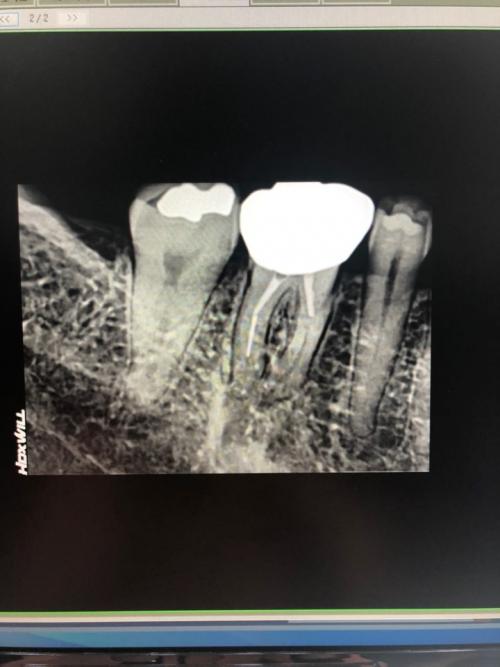

어제 2월사진과 비교해보라고 조언해주셔서 사진은찍어왓어요 혹시 한번 봐주실래요 ㅠㅠ아래가 오늘찍은거고 위가2월달에 찍은거요 ..문제는 다른치과에서 치료하면 다시 60만원을 다 내야하고 ㅠㅠ양심치과에서 as해주면 좋을텐데 말이나 해볼려고 하는데 머라고 해야할지도 모르겠고